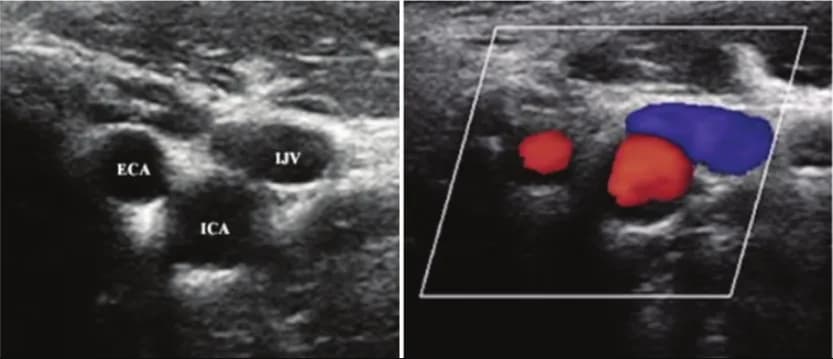

- Siêu âm Doppler: Đánh giá mức độ hẹp tắc và lưu lượng máu trong động mạch.

- Thường được thực hiện qua động mạch đùi dưới hướng dẫn của siêu âm để đảm bảo chính xác và an toàn.